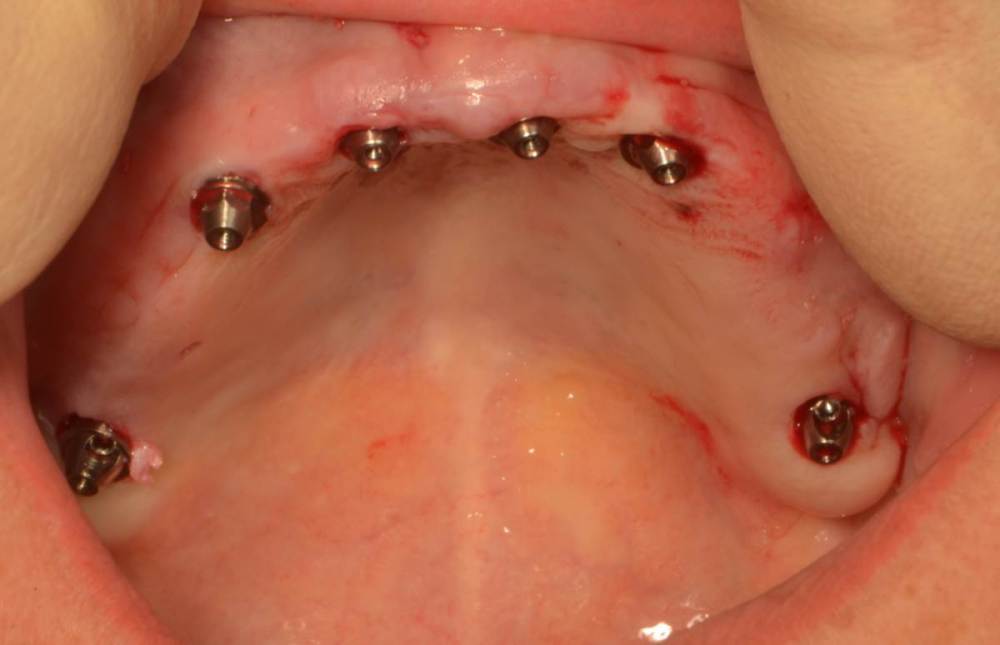

Большой Зеленый Опубликовано 2 октября, 2023 Автор Поделиться Опубликовано 2 октября, 2023 Зубы удалил предварительно. Толкать импланты в гной нехорошо. Ссылка на комментарий

Мартовский Опубликовано 2 октября, 2023 Поделиться Опубликовано 2 октября, 2023 Там везде гной был или только в 14? Лучше зубы использовать для первого шаблона для правильной постановки пинов. А потом удалить и поставить второй шаблон, когда ложе под пины создано, тогда точно промашки не будет. 1 Ссылка на комментарий

Большой Зеленый Опубликовано 3 октября, 2023 Автор Поделиться Опубликовано 3 октября, 2023 Везде воспаление было. зубы оставшиеся точно не помощники были. Ссылка на комментарий